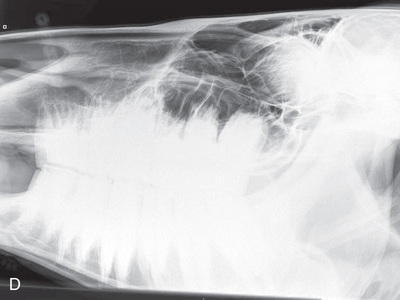

Pelvis, skull, spine, thorax, and abdomen radiographs are completed much like those in horses. In the case of a small calf, radiographs may be performed in the clinic with use of positioning and techniques similar to those used for a large dog. A mobile x-ray machine can be used to take thoracic or abdominal radiographs in a small calf (Fig. 24.62).

Small ruminant patients (sheep/goats) and swine can be radiographed much like small animals (Fig. 24.63). Because they can be easily transported, small ruminant patients are often radiographed within the clinic setting.

Because of their minimal handling experience, however, care must be taken to prevent injury due to patient response to fear (i.e., thrashing of limbs). If the patient is horned, special precautions to prevent injury to staff must be taken. Sedation is recommended to produce quality radiographs in an efficient manner.

The fleece of the ovine patient is dense and may contain dirt and debris (i.e., twigs, clumps of mud/stones). Before imaging, carefully inspect for and remove debris that may produce artifacts within the image.